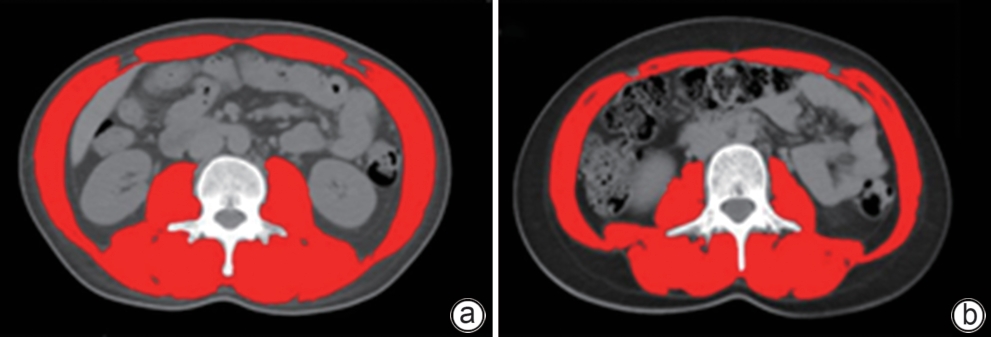

•   Objective  To establish and validate a new prediction model for the risk of death in patients with acute-on-chronic liver failure (ACLF) based on sarcopenia and other clinical indicators, and to improve the accuracy of prognostic assessment for ACLF patients.  Methods  A total of 380 patients with ACLF who were admitted to Beijing YouAn Hospital, Capital Medical University, from January 2019 to January 2022 were enrolled, and they were divided into training group with 228 patients and testing group with 152 patients in a ratio of 6∶4 using the stratified random sampling method. For the training group, CT images were used to measure the cross-sectional area of the skeletal muscle at the third lumbar vertebra (L3), and L3 skeletal muscle index (L3-SMI) was calculated. Sarcopenia was diagnosed based on the previously established L3-SMI reference values for healthy adults in northern China. Univariate and multivariable Cox regression analyses were used to establish a sarcopenia-ACLF model which integrated sarcopenia and clinical risk factors, and a nomogram was developed for presentation. The area under the ROC curve (AUC) was used to assess the predictive performance of the model, the calibration curve was used to assess the degree of calibration, and a decision curve analysis was used to investigate the clinical application value of the model. The independent-samples t test or the Mann-Whitney U test was used for comparison of continuous data between two groups, and the chi-square test was used for comparison of categorical data between two groups. The Kaplan-Meier method was used to plot survival curves, and the Log-rank test was used for comparison between groups. The DeLong test was used for comparison of AUC between different models.  Results  The multivariate Cox regression analysis showed that sarcopenia (hazard ratio [HR]=1.962, 95% confidence interval [CI]: 1.185‍ ‍—‍ ‍3.250, P=0.009), total bilirubin (HR=1.003, 95%CI: 1.002‍ ‍—‍ ‍1.005, P<0.001), international normalized ratio (HR=1.997, 95%CI: 1.674‍ ‍—‍ ‍2.382, P<0.001), and lactic acid (HR=1.382, 95%CI: 1.170‍ ‍—‍ ‍1.632, P<0.001) were included in the sarcopenia-ACLF model. In the training cohort, the sarcopenia-ACLF model had a larger AUC than MELD-Na score in predicting 90-day mortality in patients with ACLF (0.80 vs 0.73, Z=1.97, P=0.049). In the test cohort, the sarcopenia-ACLF model had a significantly larger AUC than MELD score (0.79 vs 0.69, Z=2.70, P=0.007) and MELD-Na score (0.79 vs 0.68, Z=2.92, P=0.004). The calibration curve showed that the model had good calibration ability, with a relatively good consistency between the predicted risk of mortality and the observed results. The DCA results showed that within a reasonable range of threshold probabilities, the sarcopenia-ACLF model showed a greater net benefit than MELD and MELD-Na scores in both the training cohort and the test cohort.  Conclusion  The sarcopenia-ACLF model developed in this study provides a more accurate tool for predicting the risk of 90-day mortality in ACLF patients, which provides support for clinical decision-making and helps to optimize treatment strategies.